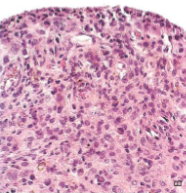

Giant cell tumor of Tendon Sheath

Most common mesenchymal neoplasm of the hand

Localized type of Tenosynovial Giant cell tumor

Involves tendon sheath of wrist, fingers, toe

Presents as a slow-growing, painless mass

May erode underlying bone

Can recur

Solid, golden/yellow nodule attached to synovium

Pathogenesis: Reciprocal chromosomal translocation, t(1;2) → fusion of type VI collagen promoter with coding sequence of Monocyte CSF gene → Overexpression of M-CSF stimulates production of macrophages

Neoplastic cells are minority of neoplasm

Majority of tumor is infiltrates of macrophages, with hemosiderin; foamy lipid; multinucleated giant cells; fibrosis may occur